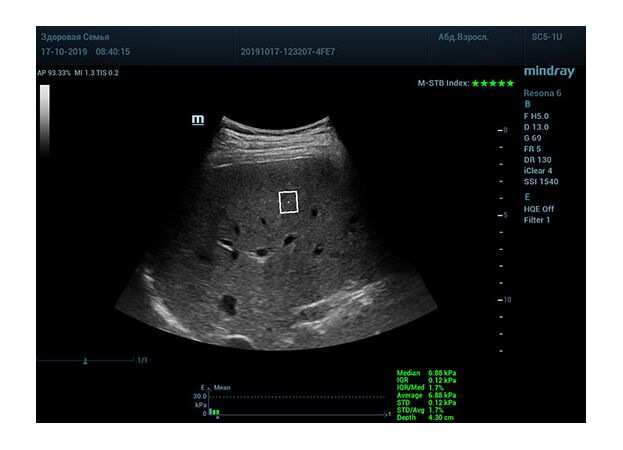

Определение плотности печени. Не ошибся ли оператор при измерении эластических свойств печени? Для оценки критериев качества предусмотрен индекс MBT, который покажет насколько «твердой» была рука оператора и двигалась ли печень. При MBT 5* рука тверда и показатели достоверны. Для оценки качества результатов используется IQR индекс, отображающий колебания показателей в точке измерения при расчете медианы. Показатели при IQR <30% считаются приемлемыми. Техника сканирования через межреберные промежутки требует размещение окна интереса на несколько сантиметром ниже капсулы, для исключения эффекта реверберации. Установка ROI на паренхиму без захвата сосудов, для исключения погрешностей измерения.